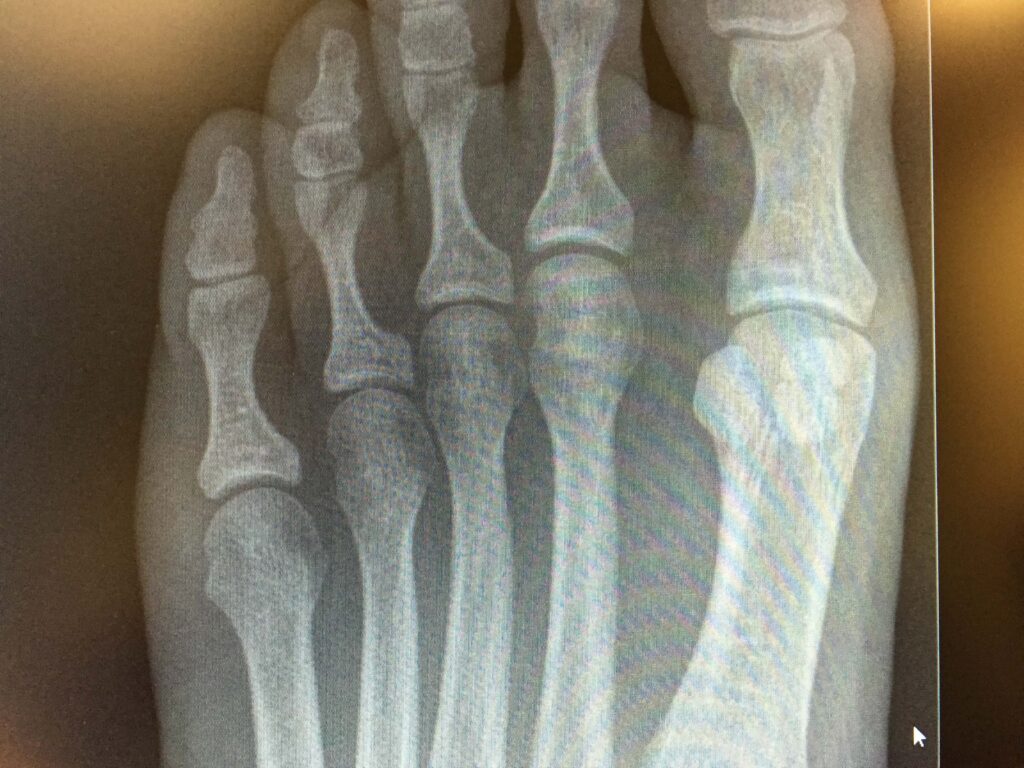

Toe Deformity Images